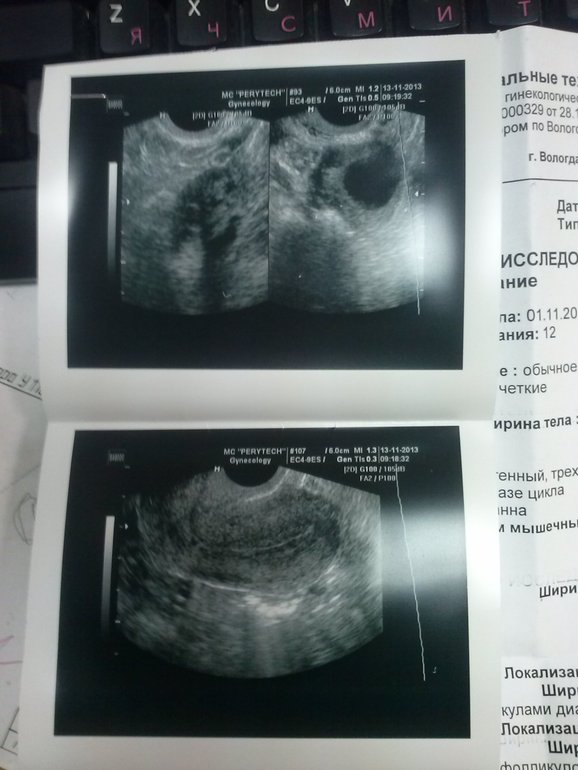

В левом яичнике определяется доминантный фолликул диаметром 17,5 мм. Моя узистка сказала ,что на сегодняшний день у меня отличная картина складывается

Но с эти пока повременим, хотя очень хочется. Вот схожу еще раз 22 числа на УЗИ, а потом 26 к Г с результатами гормонов и с этими двумя результатами УЗИ и вот тогда, надеюсь от нее получить добро. Вот собственно и протокол с фоточками) Я конечно не очень понимаю,что есть что, только догадываюсь

И кстати, эндометриоз куда-то делся,в этот раз она его не обнаружила и яичник правый встал на место )